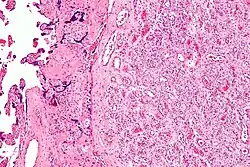

| Micrograph of a chorangioma. H&E stain. | |

- Chorangioma